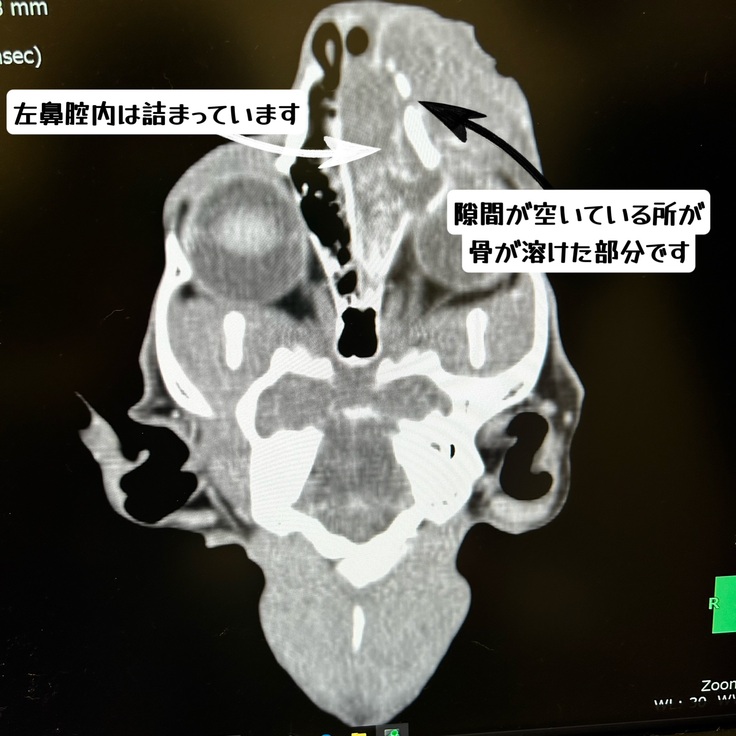

ただレントゲンやCTで、目と鼻の間の鼻がガンにより溶けていた事と腎臓への転移があった事を告げられました。

CTの鼻の写真です

でも先生が「脳浸潤はないし、右鼻腔内には転移がありません。琥珀君の場合3〜4回の放射線治療で鼻の方のガンは確実に小さくなります。腫れがなくなると食欲が出るので、放射線治療の間にたくさん食べて体力をつけて、今後の抗がん剤治療に臨みましょう。」と心強いお言葉をかけてくださり、気持ちがとても救われました。

この黒くなっている部分に放射線をあてるそうです。